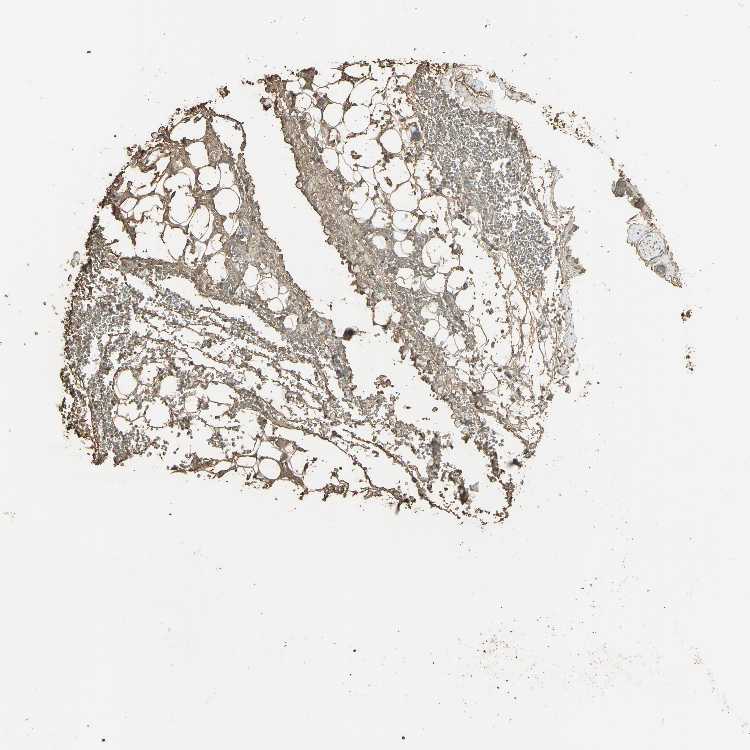

ADIPOSE TISSUE - Antibody stainingi

Antibody staining in the annotated cell types in the current human tissue is reported as not detected, low, medium, or high, based on conventional immunohistochemistry profiling in selected tissues. This score is based on the combination of the staining intensity and fraction of stained cells.

Each image is clickable and will lead to virtual microscopy that enables deeper exploration of all samples and also displays staining intensity scores, fraction scores and subcellular localization as well as patient and tissue information for each sample.

Antibody HPA006308Antibody HPA071064

Adipocytes MediumNot detected